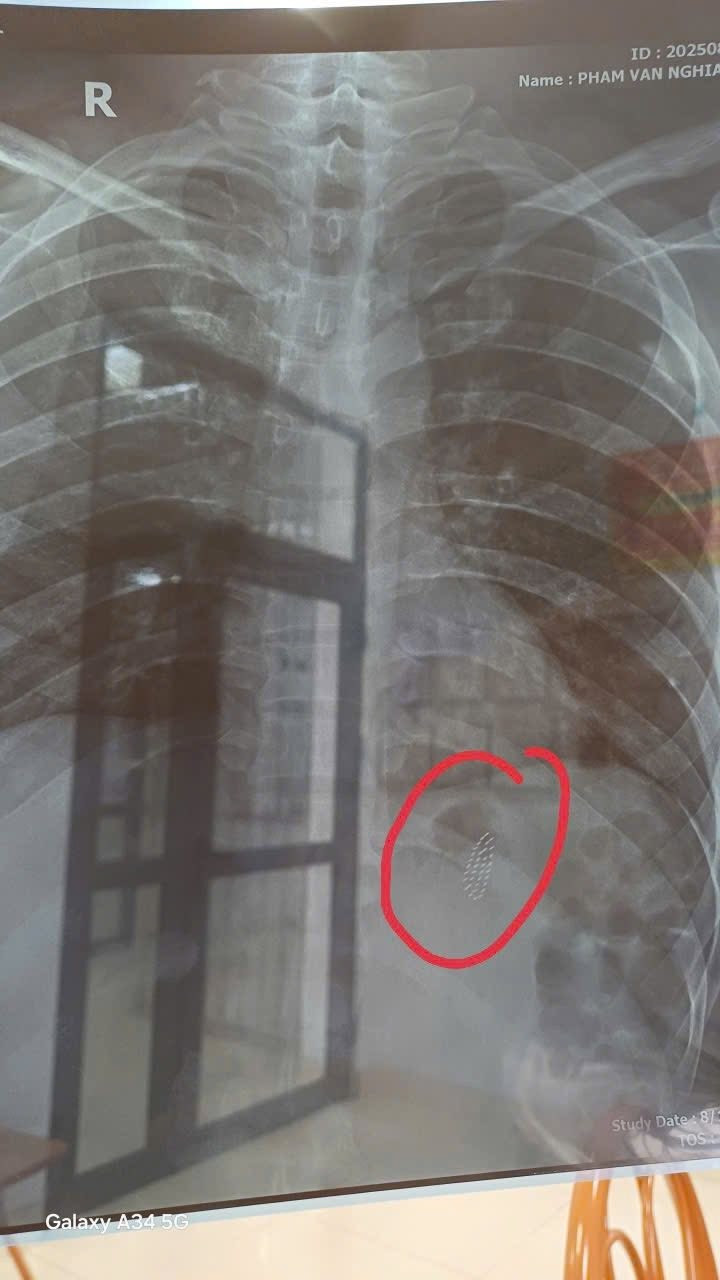

nuot-ban-chai1.jpg

Bàn chải đánh răng trên phim chụp - Ảnh BVCC

Tại đây, bệnh nhân được các bác sĩ hội chẩn khẩn cấp. BSCKII Nguyễn Huy Nam, Trưởng khoa Ngoại trực tiếp thăm khám, khai thác thông tin và đưa ra chỉ định nội soi dạ dày gây mê can thiệp để lấy dị vật, nhằm hạn chế tối đa nguy cơ thủng, chảy máu dạ dày hoặc biến chứng nguy hiểm.